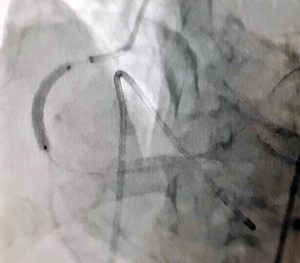

BVXA – SUÝT LIỆT NỬA NGƯỜI VÌ NHỒI MÁU NÃO. ĐIỀU TRỊ THÀNH CÔNG BẰNG THUỐC TIÊU SỢI HUYẾT KỊP THỜI.

Trưa ngày 15/5/2017, BVXA đã tiếp nhận điều trị cấp cứu bệnh nhân Đ.V.T. (sinh năm 1960 ngụ tại huyện Củ Chi, TP.Hồ Chí Minh) trong tình trạng chóng mặt, liệt nửa thân bên trái, méo miệng. Điều trị trong thời gian 1 ngày, ông T. đã khôi phục hoạt động tay chân. Trước đó, […]